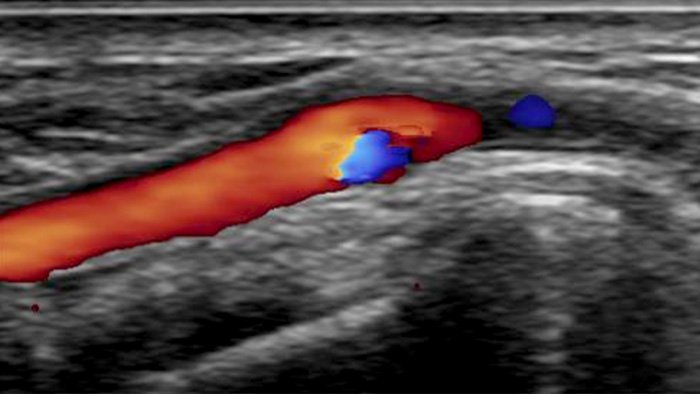

Für einen effektiven Zugang zum arteriellen System ist eine realistische Visualisierung des arteriellen Gefäßsystems erforderlich. Unser integriertes CX50-Ultraschallsystem liefert hochwertige Bilder der Radialarterie und -venen, um radiale Zugangsinterventionen zu unterstützen.